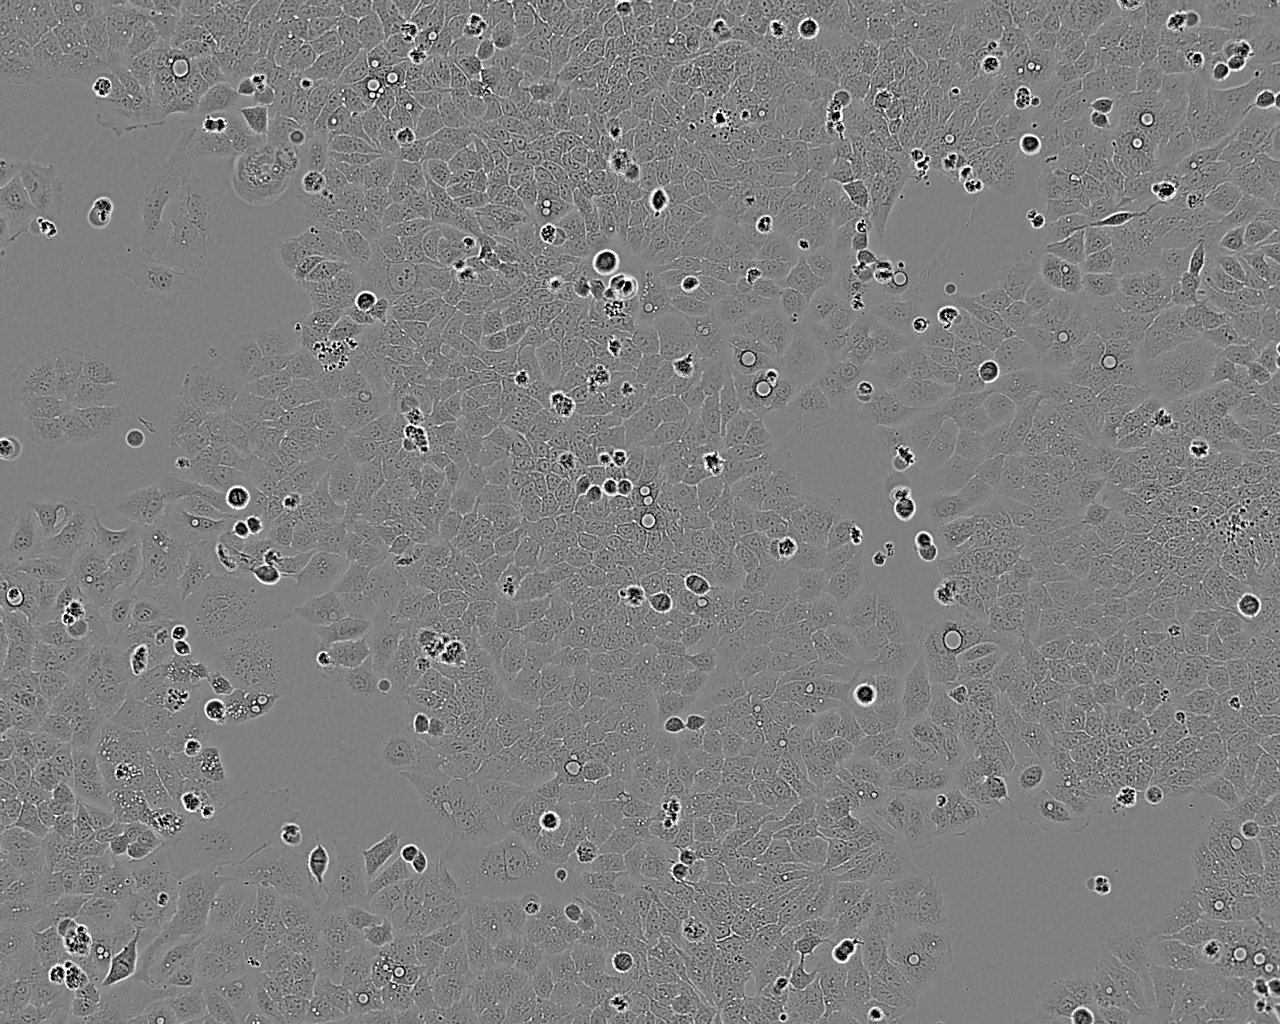

• 5-8F 鼻咽癌细胞系

细胞形态:上皮细胞样

细胞生长:贴壁

细胞生长特性:贴壁生长